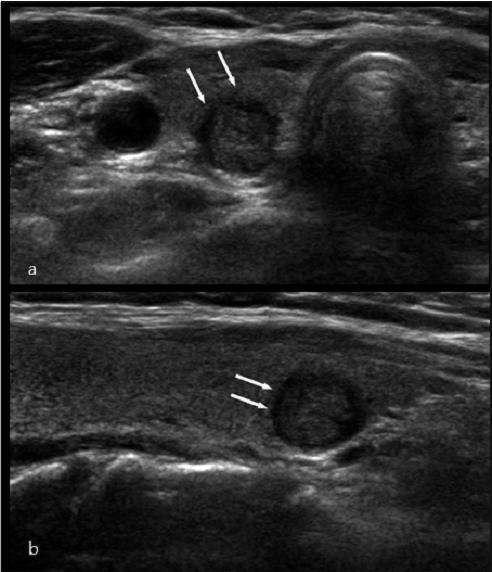

图1 甲状腺胶质囊肿内部胶态晶体后方的"彗星尾征".

甲状腺结节横轴声像图,其内见数个点状强回声灶,至少 个见彗星尾征

内部回声均匀(如图1),网状或蜂窝状,彗星尾征等,而恶性甲状腺结

77甲状腺内大部分为良性病变,有点状强回声伴彗星尾征,但是也有少数